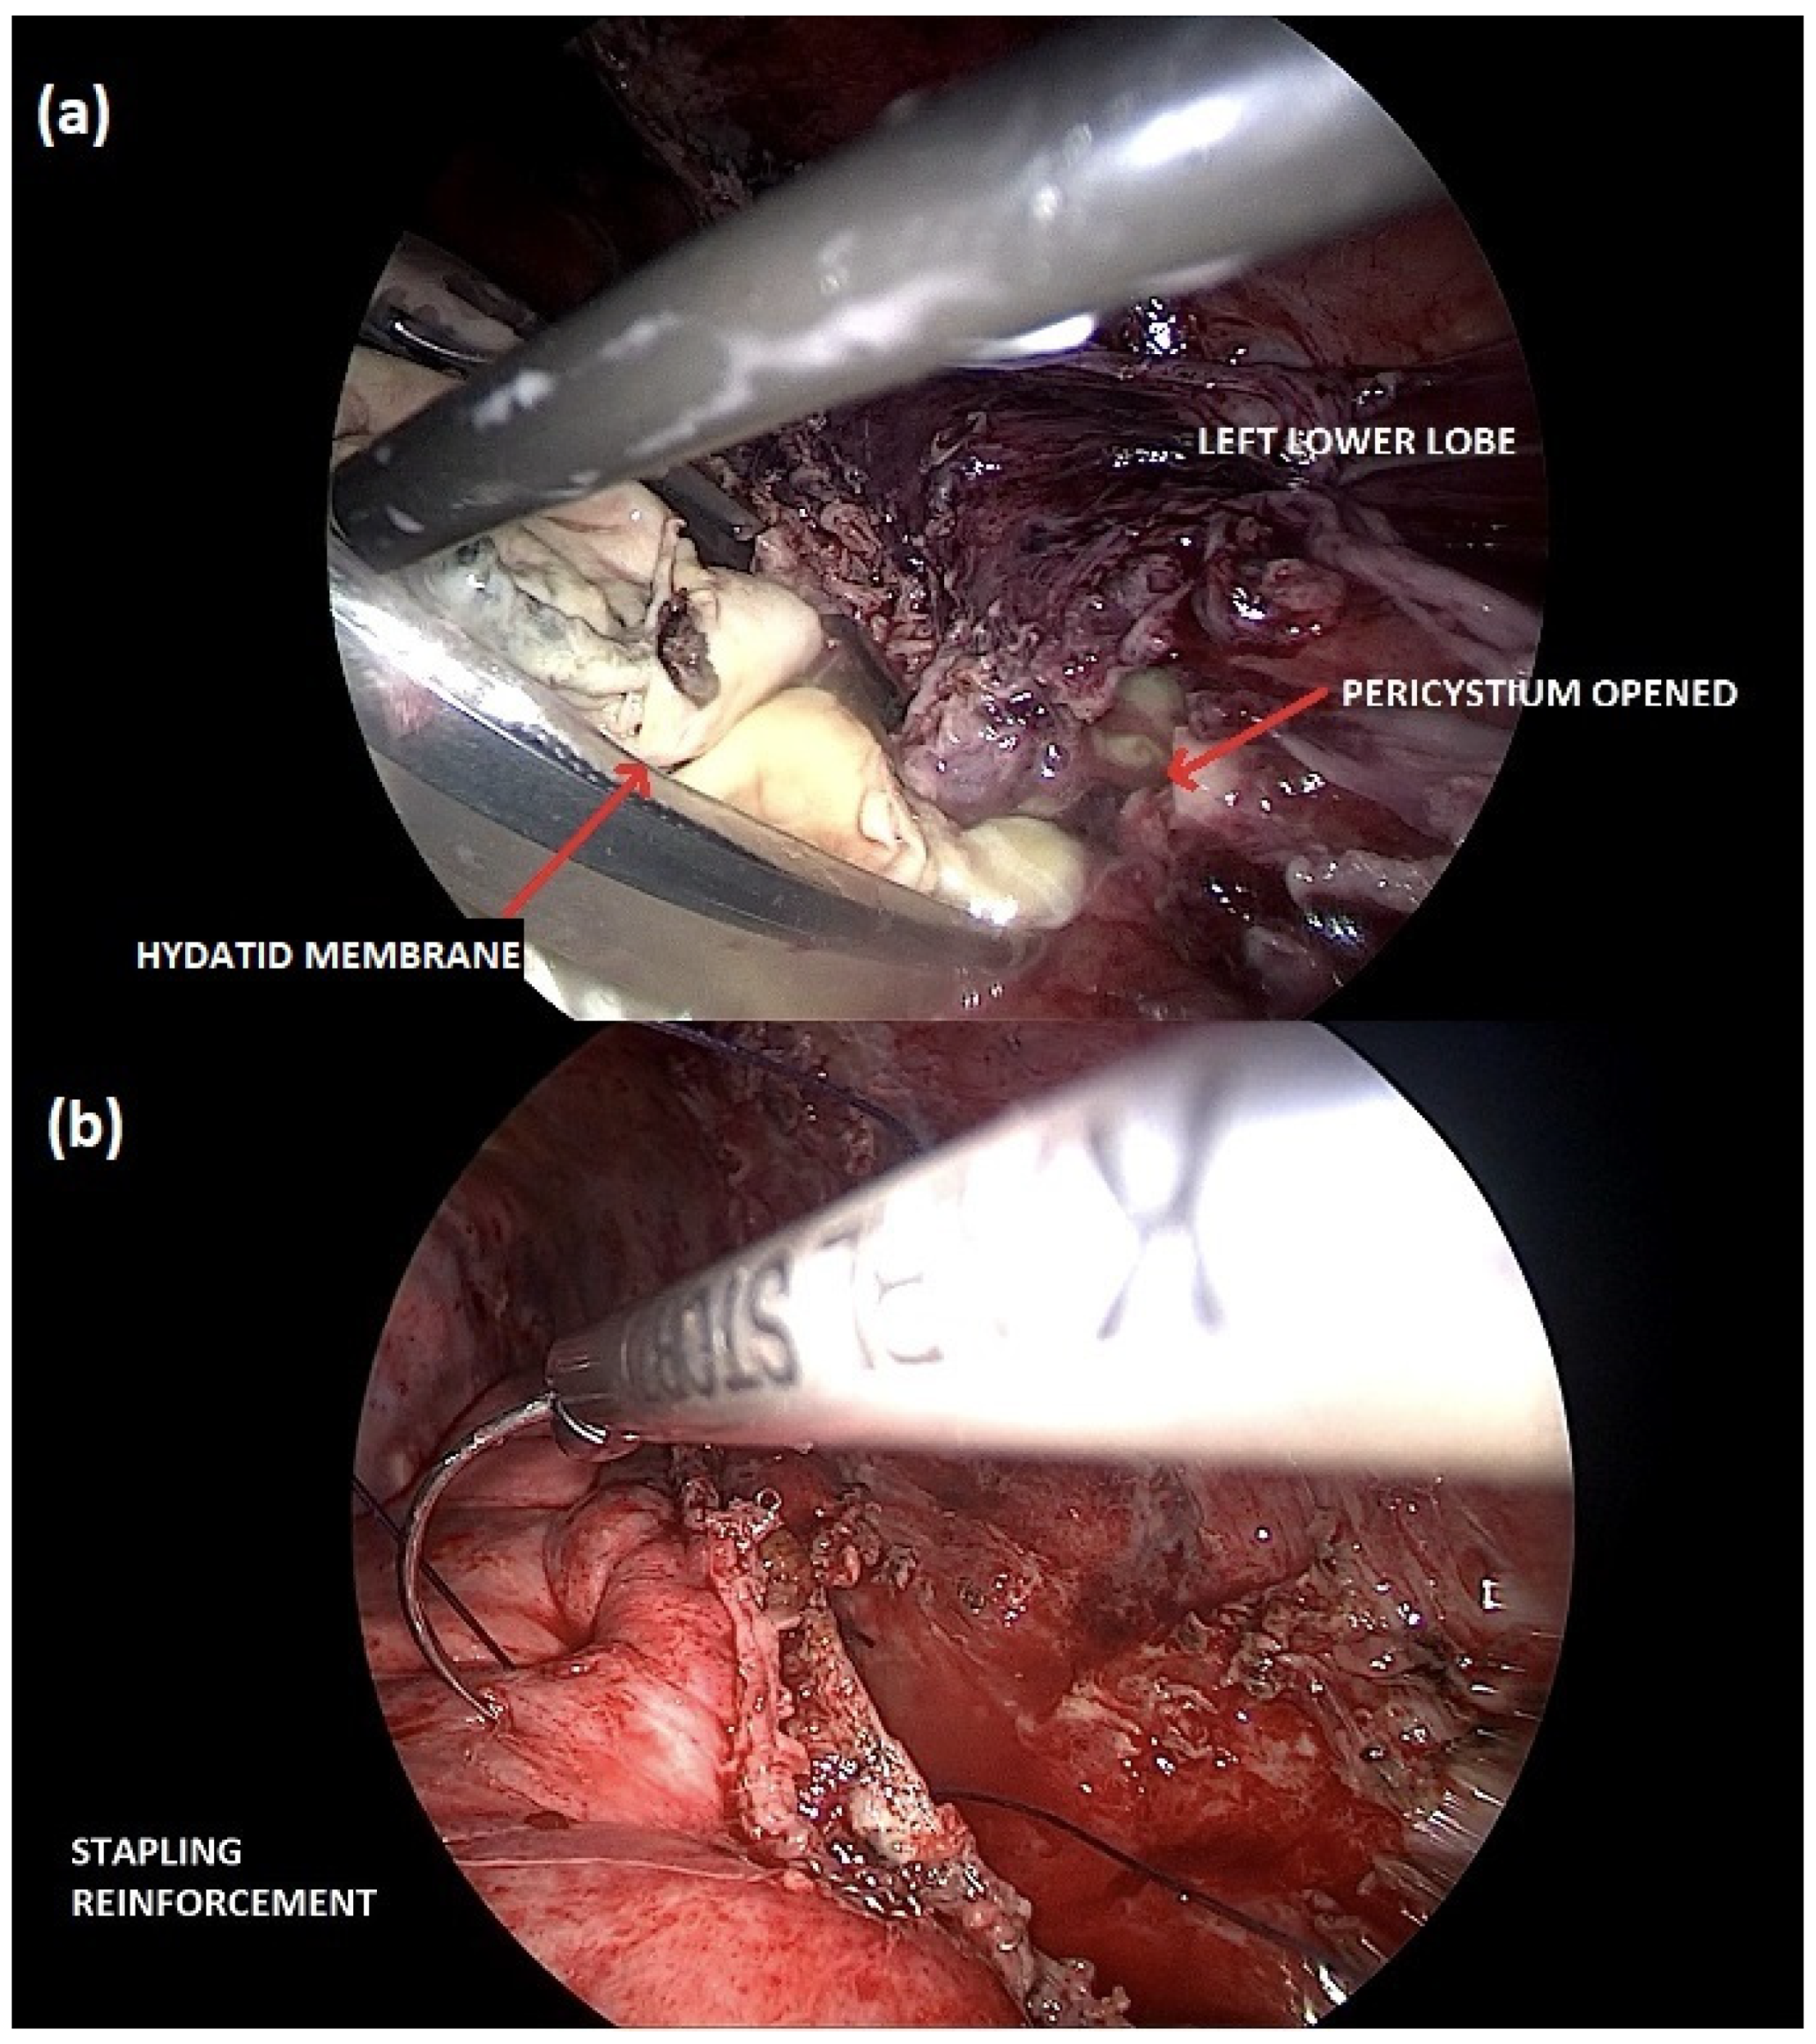

2. Case Description